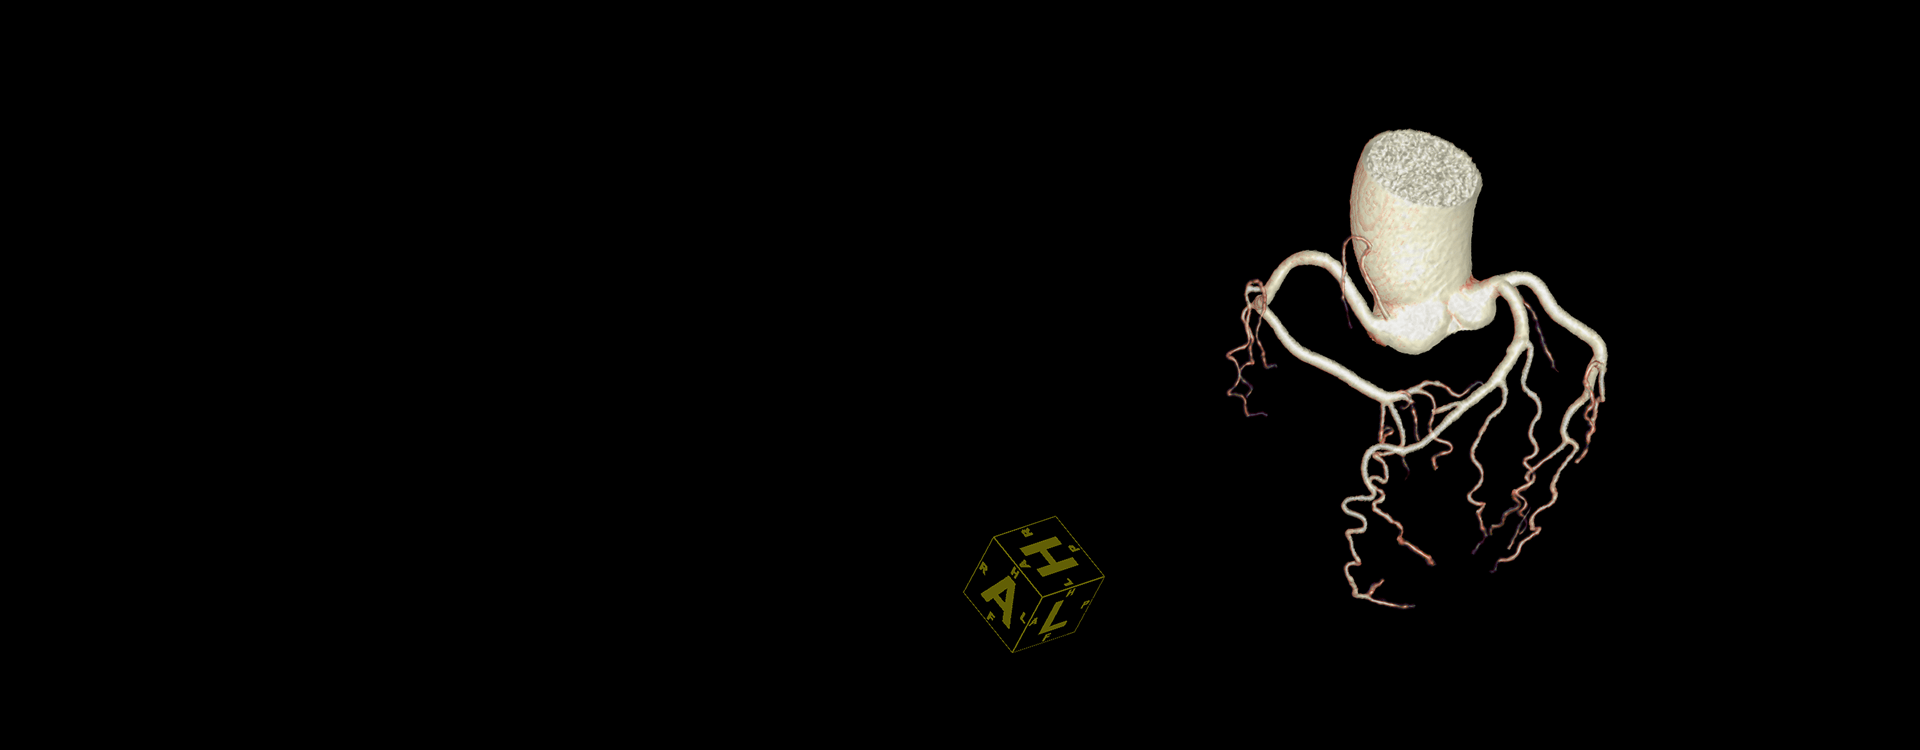

CT心血管分析

具备冠脉提取、斑块分割、狭窄标记、心功能计算等多种功能,可清楚显示冠脉及其管径轮廓,并进行定量计算结果显示